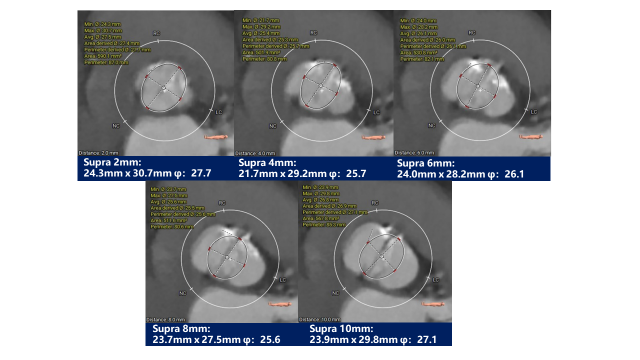

瓣上测量

瓣上测量:瓣叶中重度钙化伴增生肥厚,钙化呈偏心性分布,主要分布于瓣叶边缘及前壁交界附着缘。

3. 依据瓣环及瓣上测量结果,给予23mm球囊进行预扩张,预装AV31瓣膜;术中结合球囊扩张情况进一步明确瓣膜尺寸选择;